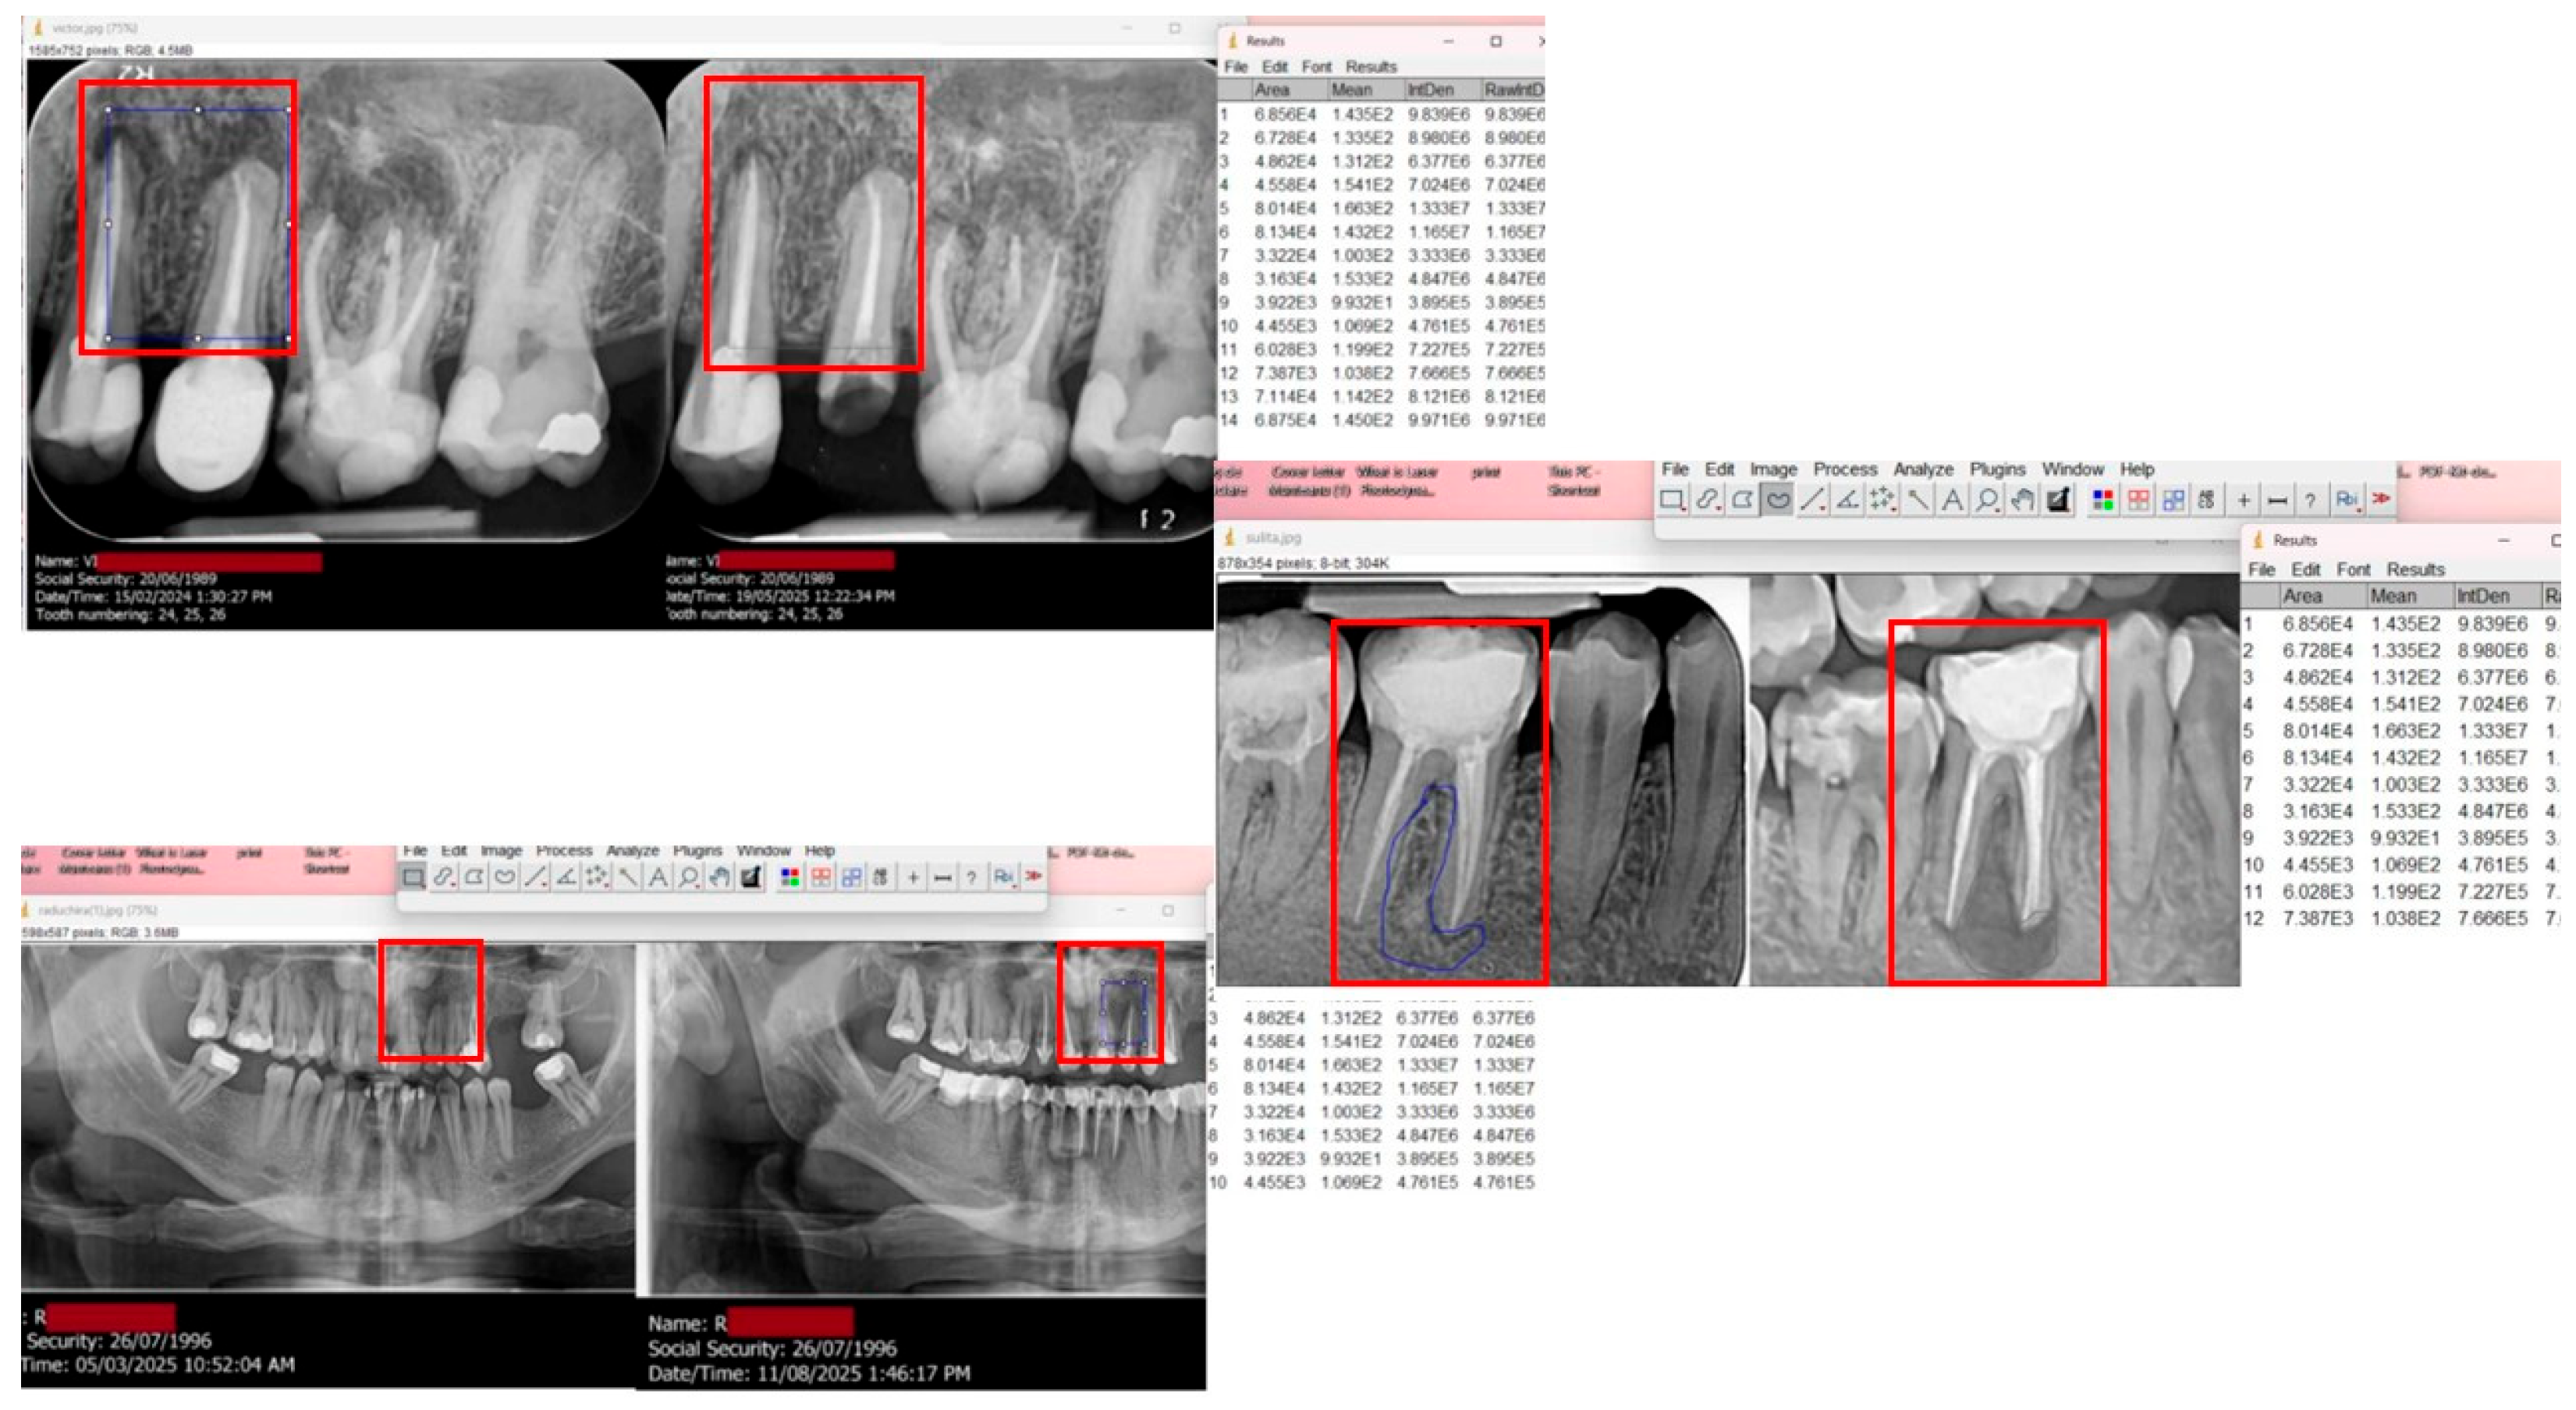

Radiographic Evaluation

| ROI | Region of interest (for image analysis) |